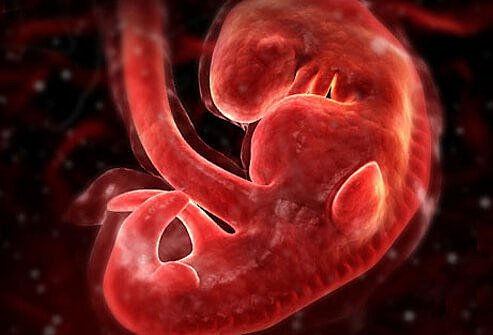

• First Month

First Month

By the end of the two weeks, the fertilized egg is about the size of a pin head. The heart, which is no larger than a poppy seed, has begun beating. The egg has attached itself to the lining of the uterus.